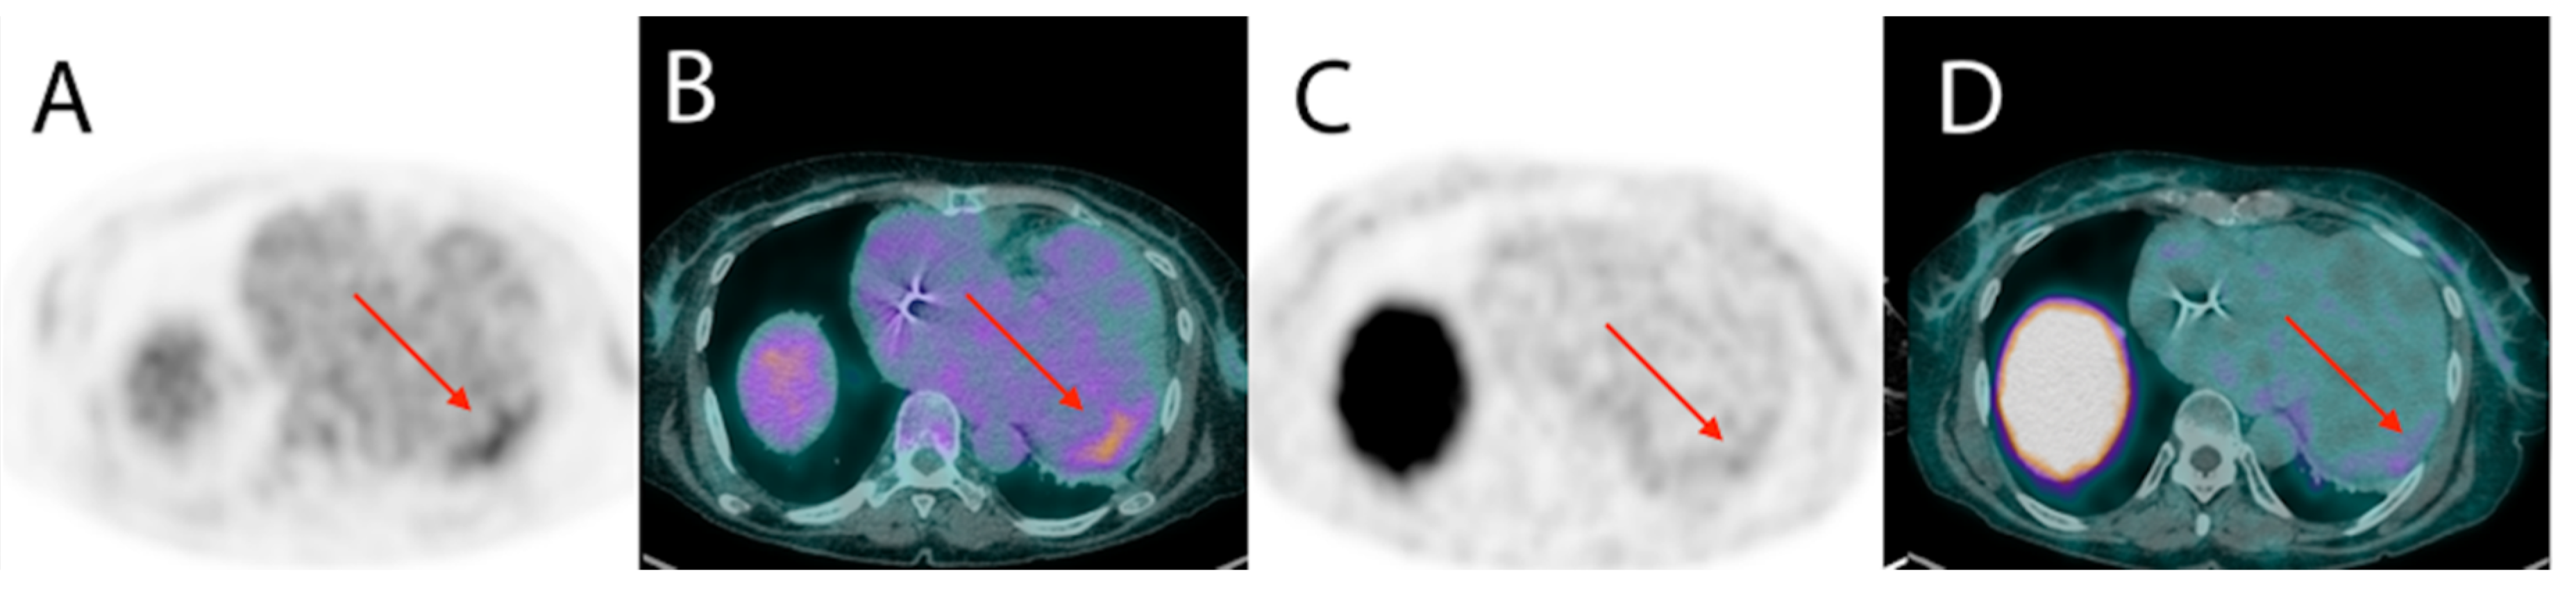

6. Nuclear Medicine